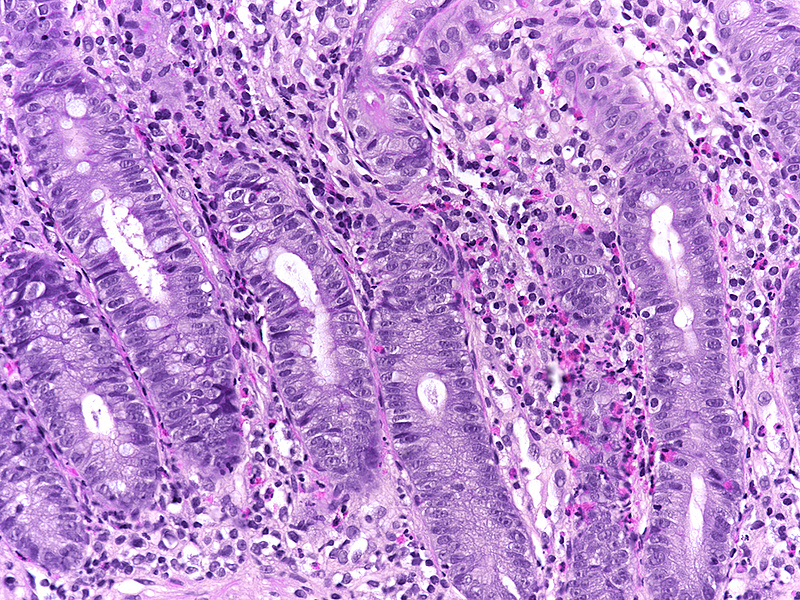

Biopsy material from the right colon in a 48-year-old male.

NSAID colonopathy.

Histologically, the architecture of the mucosa showed mild architectural distortion. The cell content within the mucosa was increased, with predominance of monuclear cells, that is, lymphocytes and plasma cells (Panels A-B). High magnification revealed mild basal plasmactytosis and additional neutrophil granulocytes in stroma and crypt epithelium (cryptitis) as well as clusters of eosinophils (Panel C). The crypt epithelium showed reactive changes, with loss of goblet cells, variation in nuclear size with small nucleoli, and increased apoptosis. Withered crypts were only occasionally seen (Panel D). Superficial erosion and regenerative epithelium were identified in the coecum (Panel E), with rare superficial intracapillary fibrin thrombi (Panel F).

Within the colon, several pattern may be observed. They all have in common that the right colon, in particular the region around the ileocoecal valve, is predominantly affected. Changes that are comparable to early inflammatory bowel disease (“incidental chronic colitis”) may be seen, but transmucosal increase of chronic inflammatory cells with basal plasmacytosis and architectural distortion are generally mild. Intraepithelial lymphocytes may be found to be increased (up to the morphology of lymphocytic colitis, with or without subepithelial collagen deposition). Mucosal defects, erosions and/or ulcers, may demonstrate a somewhat ischaemic picture (due to impaired microcirculation), and rarely, as in this cage, intracapillary microthrombi may be found. The combination of these findings with eosinophils and increased crypt cell apoptosis should ultimately raise the suspicion of drug-induced changes.